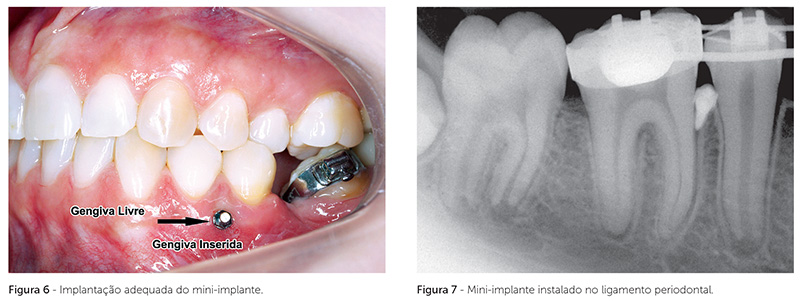

Para que a perda do mini-implante não ocorra em função da deflexão óssea alveolar, esse deve ser colocado o mais próximo da parte mais basal do processo alveolar, ou seja, na parte correspondente ao terço apical das raízes. Nessa região, o volume ósseo, a espessura das corticais e a maior densidade e espessura das trabéculas impedem que ocorram movimentos estruturais resultantes da deflexão óssea. Entretanto, clinicamente, isso nem sempre é possível, pois o mini-implante deve ser preferencialmente implantado em gengiva inserida, propiciando maior conforto ao paciente (Fig. 6)2.

A proximidade ou relação direta do mini-implante representa um contato e atrito entre uma parte móvel — o dente — e uma parte fixa (Fig. 7), promovendo rompimento de vasos, células e fibras, e instalação de um constante e renovado estímulo à inflamação do local, o que resulta em reabsorção óssea peri-implantar e perda de seu imbricamento mecânico.